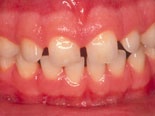

Före och efter behandling med kompositfasader.